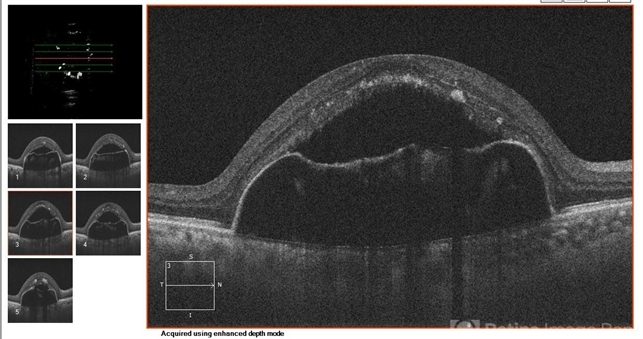

- optical coherence tomography (OCT)

- Eitae Kim, BOIM retinal center, Pureun eye hospital

Optical coherence tomography system

Cirrus, Zeiss - Description

- OCT of 78-year-old male with advanced AMD after 6 injections of bevacizumab.